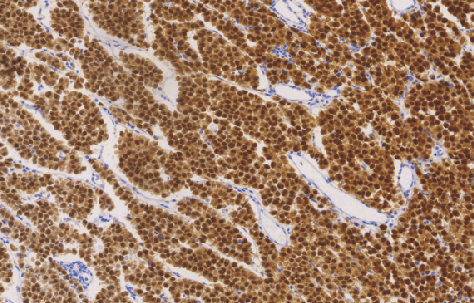

OCT3/4鼠抗人OCT3/4单克隆抗体

OCT3/4是一种POU结构域的转录因子,具有多分化的潜能。在胚胎干细胞与生殖细胞中具有较强的表达,在分化后体细胞中逐渐减弱。该抗体主要作为精原细胞瘤、中枢神经生殖细胞瘤的诊断指标,同时也作为无性细胞瘤鉴别的重要指标之一。

- 阳性部位:胞核

- 适用组织:石蜡切片

- 预处理:热修复